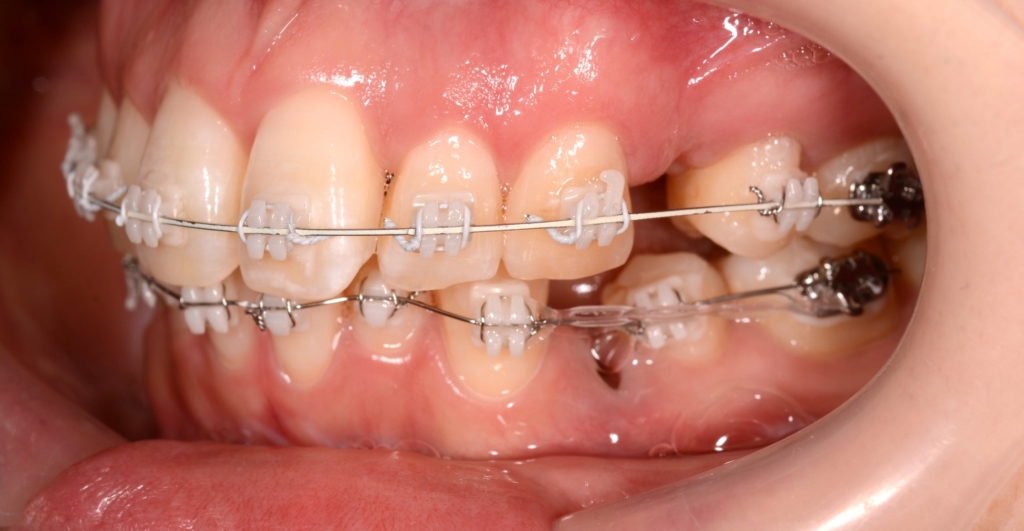

そうこうしているうちに、下の歯列も並んで整ったので、

「上の前歯の圧下」と「下の前歯の後方への移動」を同時進行で行うことにしました。

その後、ガミースマイルの改善が済んだので、あらためて「上の前歯も後方への移動」を行いました。